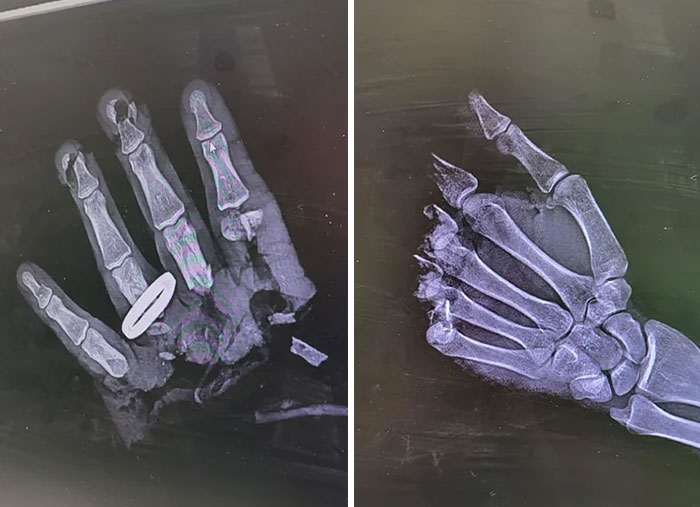

Chainsaw Accident On X-Ray

Thumb Pinched In Ski Binding!